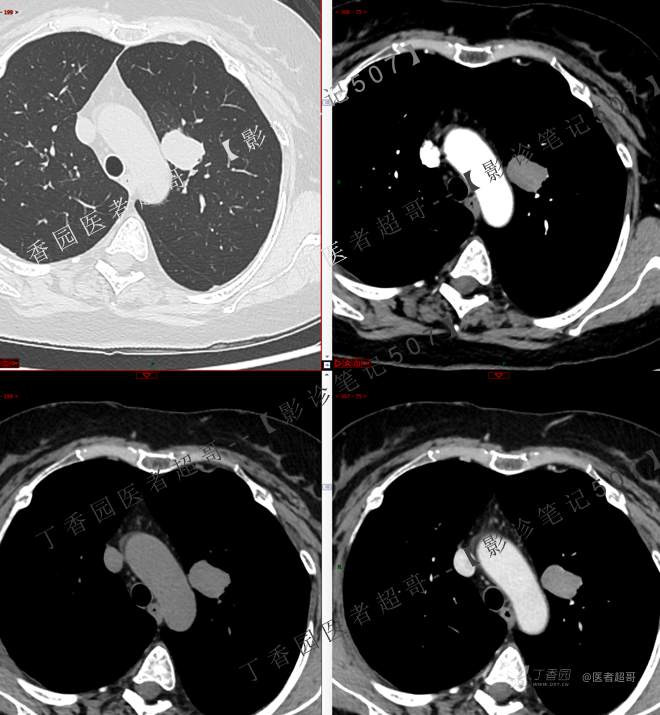

患者性别:女

患者年龄:50岁

简要病史:患者4月余前出现无明显诱因及病因出现胸痛,无咳嗽咳痰等表现。